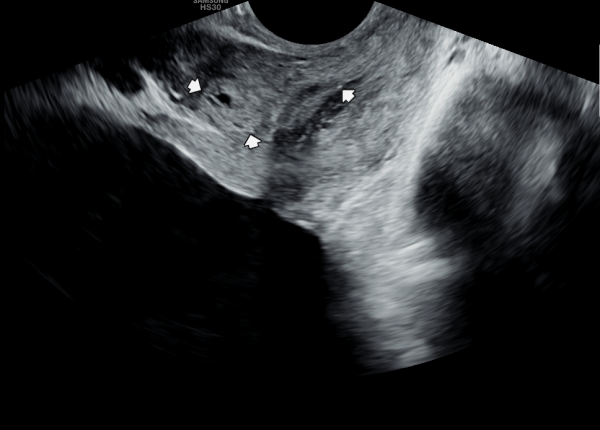

수년전부터 회음부 통증과 배뇨 장애로 내원 당일 검사한 경직장 전립선 초음파 검사상 사정관 입구의 미세 결석과

전립선의 낭종이 관찰되는 초음파 사진입니다.

A transrectal prostate ultrasound image taken on the day of the visit shows microcalcifications at the opening of the ejaculatory duct and cysts within the prostate, in a patient who had been experiencing perineal pain and voiding difficulties for several years.